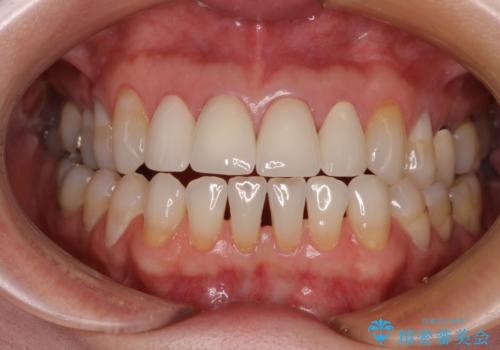

前医で仮歯を装着する前の口元の写真をいただき、咬み合わせや形態を参考にしながら仮歯で仕上がりをイメージし、最終的に満足のいくオールセラミッククラウンを装着することができました。